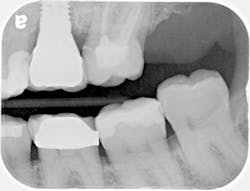

A 55-year-old female presented to my office for an evaluation of a crown placed on tooth No. 15 within the last few years. Her complaints included: "It feels big. I get a ton of food trapped in it, and it is kind of ugly." A bitewing was taken (Fig. 1) revealing an ill-fitting crown on No. 15. An intraoral photo was also taken (Fig. 2) confirming an oversized PFM with poor contours. The decision was made to remove and replace the crown.

FIG. 1